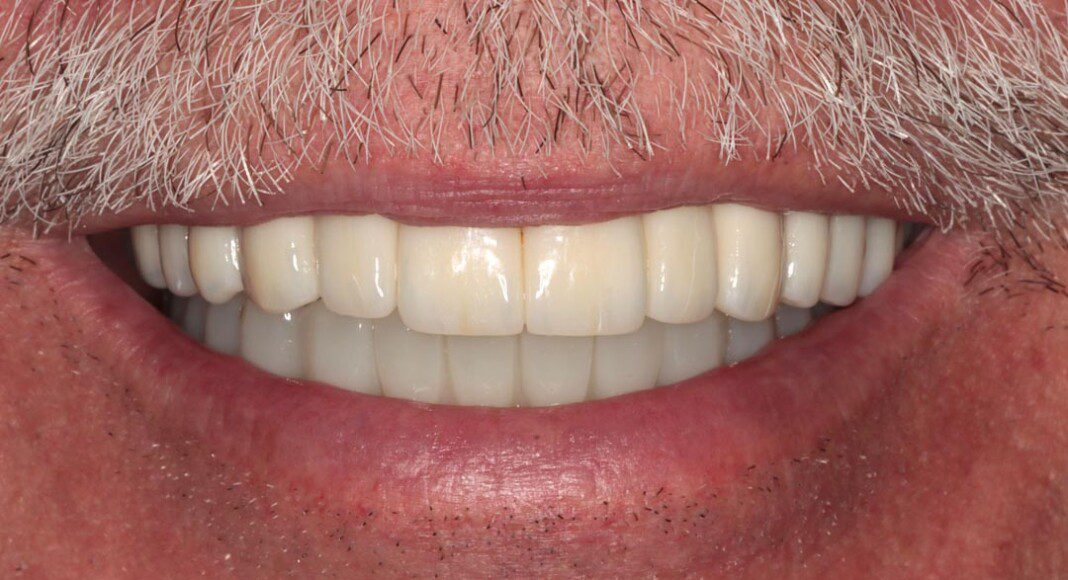

Prototype try-in, smile. The temporary bridges are removed and the prototypes placed. This is where the most scrutiny takes place as we want the patient and family to be thrilled with the appearance and bite. This is the last time changes can be made.